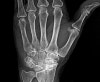

MRI : 주상골 골절(Scaphoid fracture)

여기에서도 정상이면서 통증이 2~3주간 지속되면 반복해서 X-ray 검사를 하고(>10% of cases : Repeat imaging in 2 weeks will often show fracture) MRI 검사를 합니다.

X-ray 소견이 정상일지라도 코담배갑의 압통이 심하면 주상골 골절로 간주하고 엄지와 손목관절을 같이 고정하는 보조기(thumb spica splint)를 해줍니다. 이후 X-ray 검사를 반복적으로 촬영하거나 MRI 검사에서 골절을 확인할 수 있습니다(치료가 빠를수록 불유합이 위험이 감소하기 때문에 초진 시부터 부목고정을 하는 것이 좋습니다).